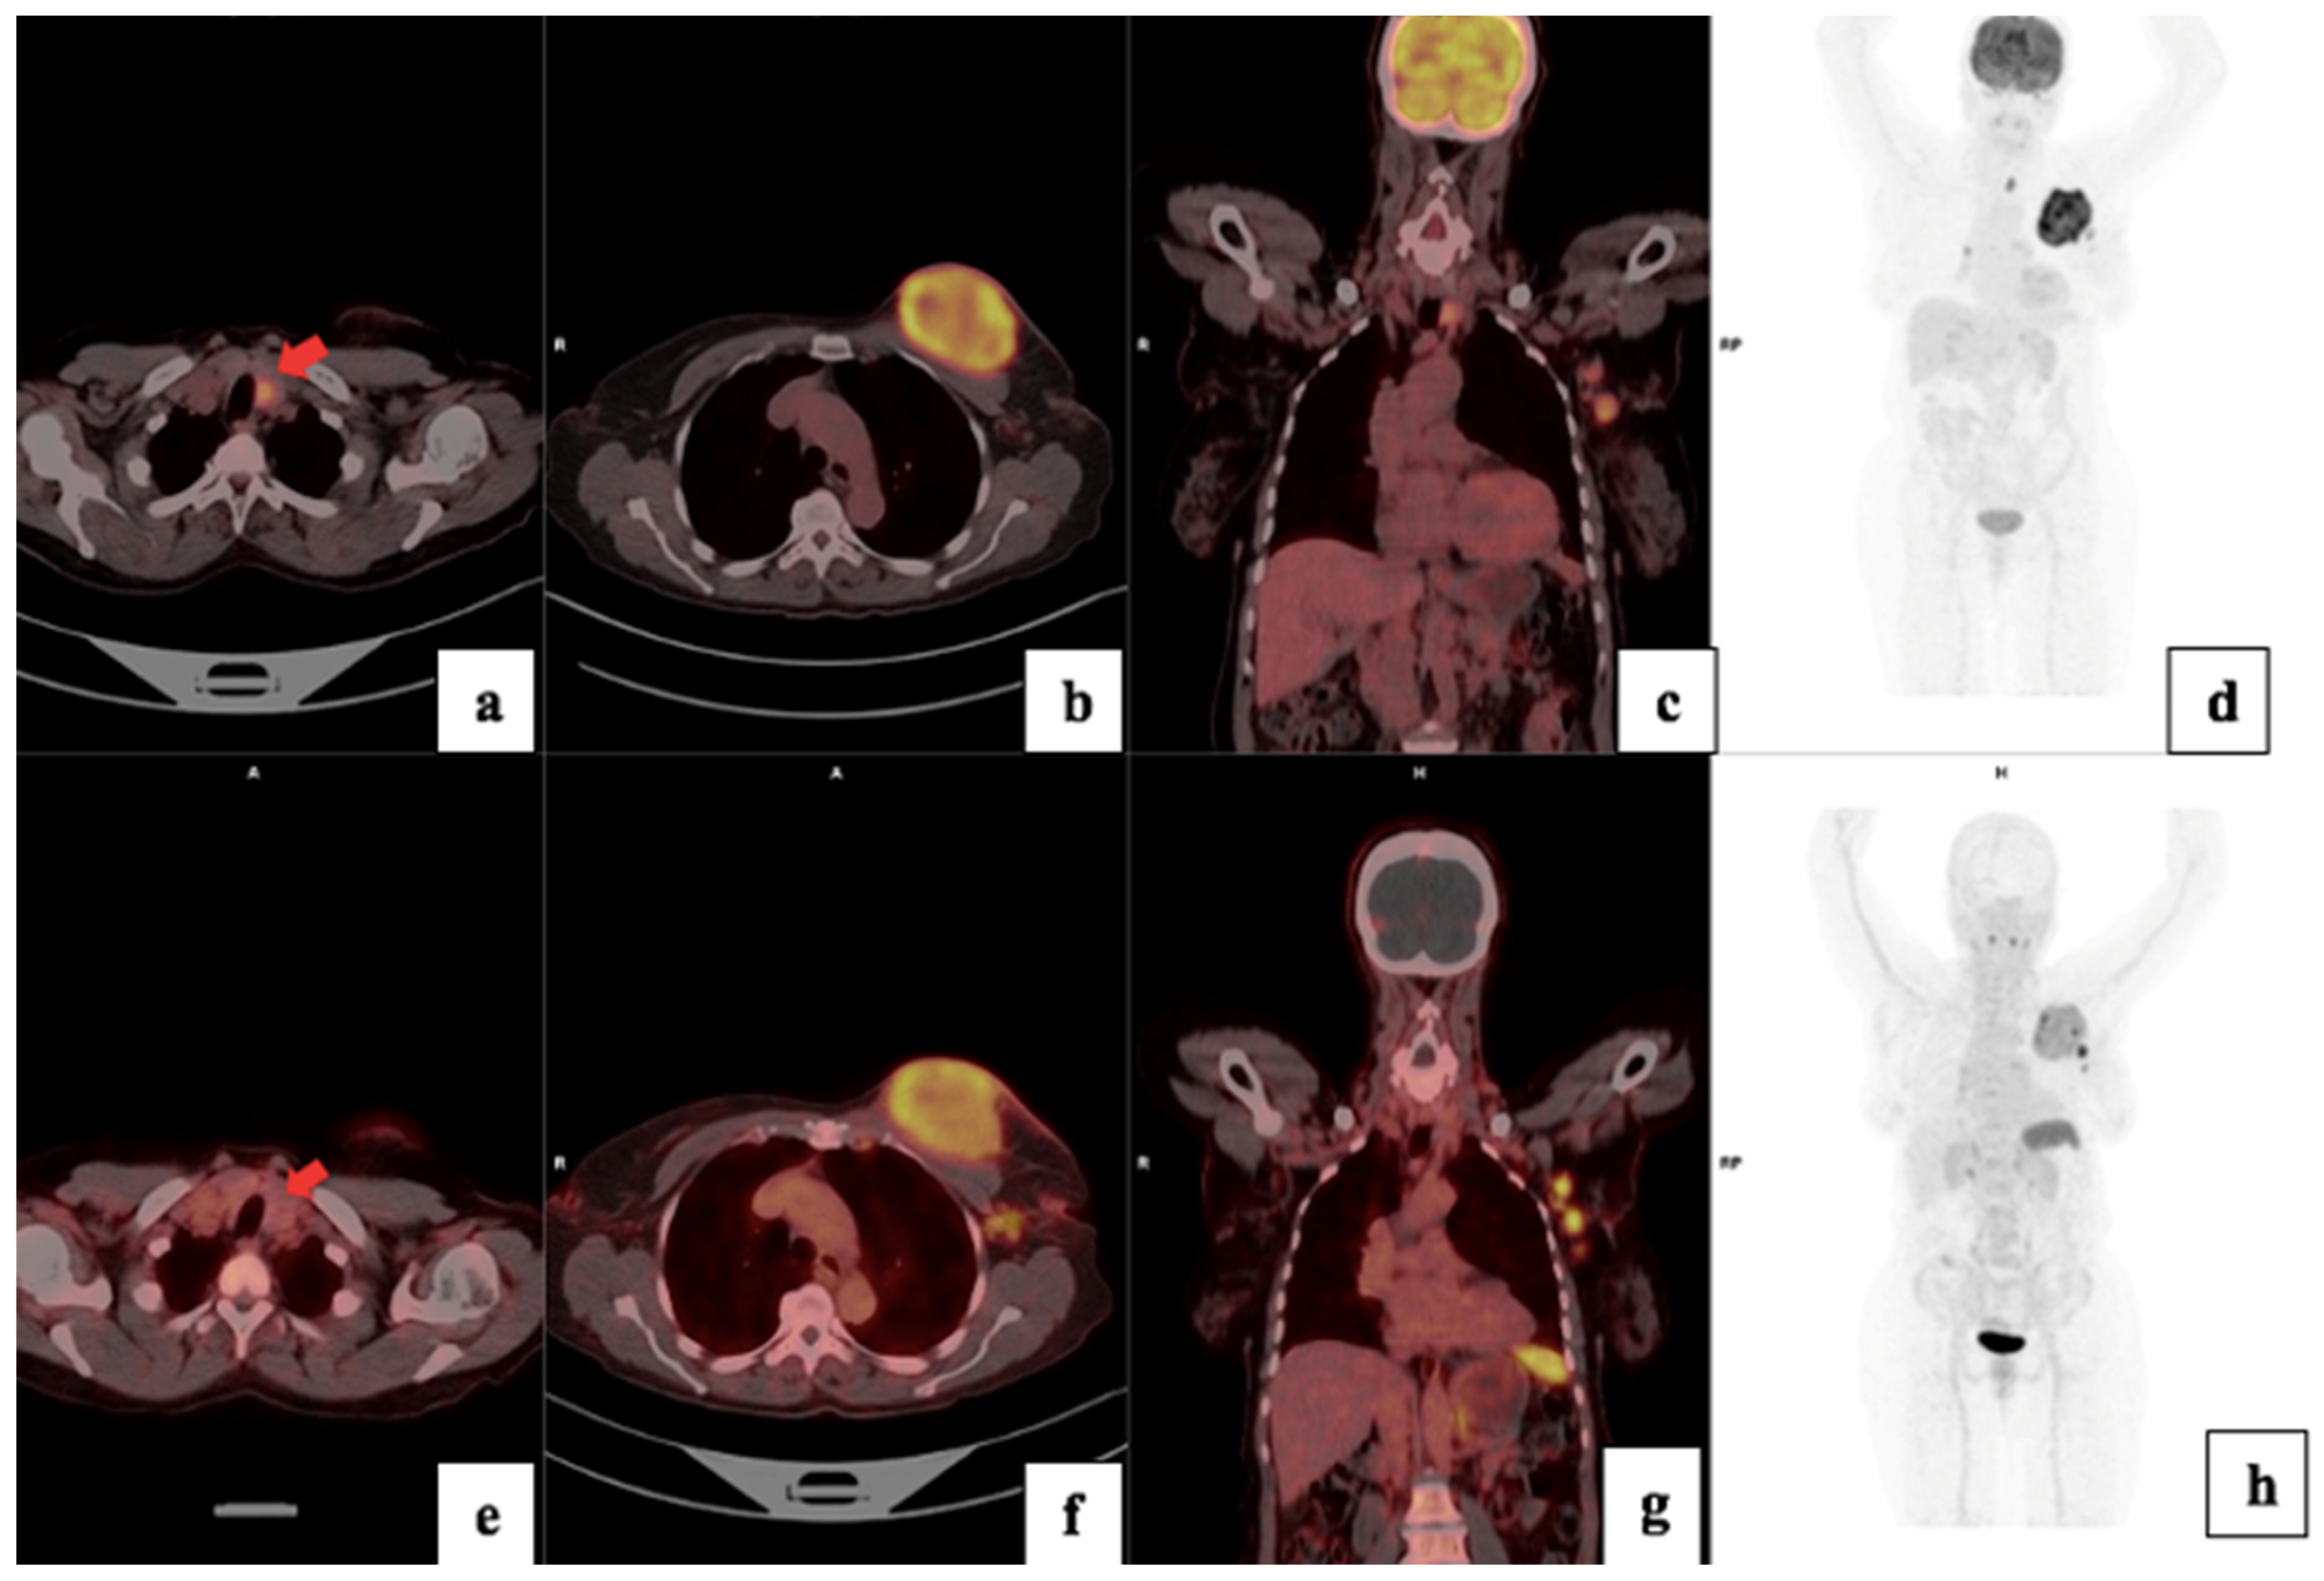

3.4. Visual Analysis

3.5. Treatment Response